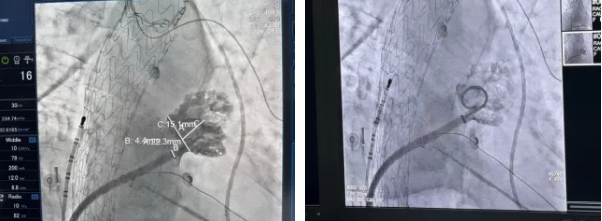

11月22日,錦州市中心醫(yī)院心內(nèi)四科起搏電生理團隊在心腔內(nèi)超聲(ICE)引導下,成功完成“房顫射頻消融術”+“左心耳封堵”一站式手術兩例,該手術是目前治療房顫的先進技術,一方面可解決患者房顫癥狀問題,另一方面雙保險預防房顫卒中風險,將患者卒中和出血風險降到最低。手術的成功標志著我院在電生理技術創(chuàng)新上的重大突破和進步,將為更多房顫患者帶去更安全更高效的治療。

經(jīng)充分與患者溝通后,屈春紅主任團隊在天津總醫(yī)院蔡衡主任指導下,成功為兩位患者實施了ICE引導下“房顫射頻消融術”+“左心耳封堵”一站式手術,一次手術解決兩個難題。術后,患者迅速恢復了竇性心律,胸悶等不適感也隨之消失。

心房顫動(房顫)是最常見的持續(xù)性心律失常,增加了死亡、卒中、心力衰竭(心衰)、認知功能障礙和癡呆風險,嚴重影響患者生活質量。目前最新指南共識均強調(diào)房顫綜合管理:節(jié)律控制與卒中預防。導管消融是目前房顫治療的優(yōu)選方案且常規(guī)首選一線治療手段(IA類推薦),在我國已開展近30年。預防房顫患者發(fā)生卒中的常見手段為左心耳封堵術,該手術能夠有效解決傳統(tǒng)藥物治療存在的局限性。

“一站式”手術可以同時對房顫患者進行節(jié)律控制和卒中預防,該手術具有安全高效等諸多優(yōu)勢。且一次手術完成兩項治療,節(jié)約手術時間,提高治療效率同時有效減少患者反復就醫(yī)成本,使患者獲益最大化。